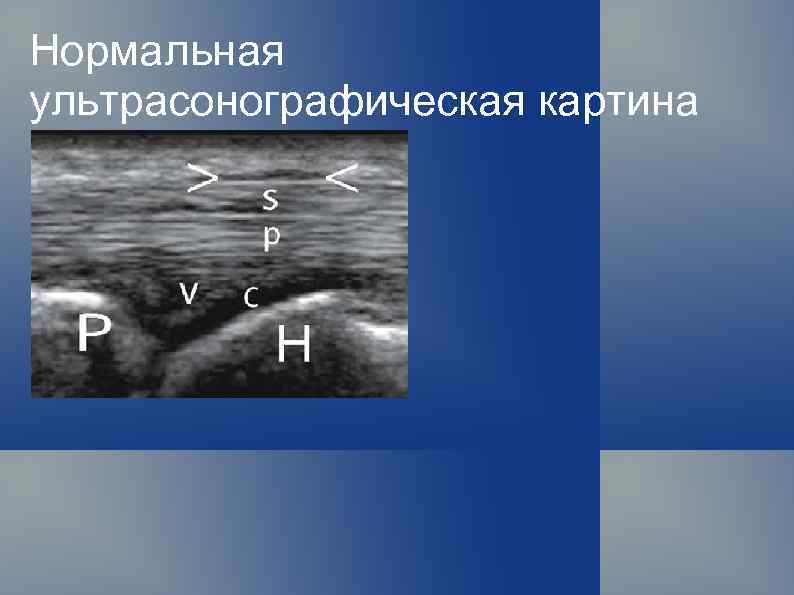

Нормальная ультрасонографическая картина Кожа и подкожная клетчатка

Нормальная ультрасонографическая картина